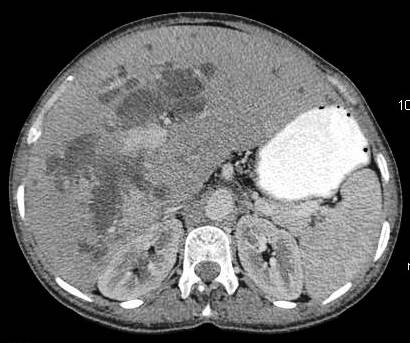

Common patterns of carcinoma gallbladder

Three patterns have been described on ultrasonography (US). The gallbladder fossa is replaced by a heterogeneous mass (figure 1) with internal areas of necrosis; or there may be diffuse, irregular, and asymmetrical wall thickening (Figure 2); or less commonly, a polypoidal, fungating intra-luminal mass is seen. Correct preoperative diagnosis has improved considerably with the use of newer imaging techniques [6-8]. Majority of cases when diagnosed, are no longer resectable (Figure 3) [9-11].

Figure 2: diffuse infiltrative carcinoma of the gallbladder with irregular wall thickening and invasion of liver parenchyma. Medially the plane with second part of duodenum is invaded. Inferiorly right perinephric fat plane invaded